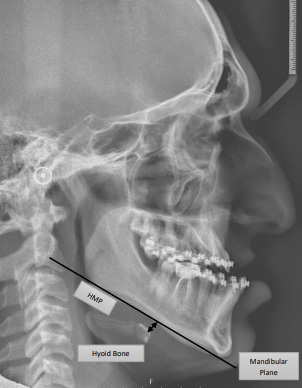

One of the anatomical features, the inferior-dorsal position of the hyoid bone, which is measured via CEPH,23, 24, 25 and expressed as the hyoid bone–mandibular plane distance (HMP) in millimeters, is suggested to be of importance in some patients with OSA.26, 27, 28 One of the parameters for measuring the hyoid bone position in CEPH is the perpendicular distance from the most superior-anterior point on the body of the hyoid bone (H) to the mandibular plane (MP), which is constructed by connecting the lowest point on the lower border of the mandibular body (gnathion) and the lowest point on the lower border of the mandibular ramus (gonion), the reference point on the C3 being the most inferior-anterior point on the body of the C3 (Figure 1).29 The average HMP value in the healthy population is 9.03 ±3.92 mm, whereas it amounts to 22.81 ±6.76 mm in OSA patients.30 It has been found that HMP is longer in patients who suffer from severe OSA as compared to those who do not.31According to a meta-analysis conducted by Neelapu et al., there is an average difference of 4.0–6.6 mm in HMP between patients with OSA and those without it (controls), with OSA patients having a longer HMP.28